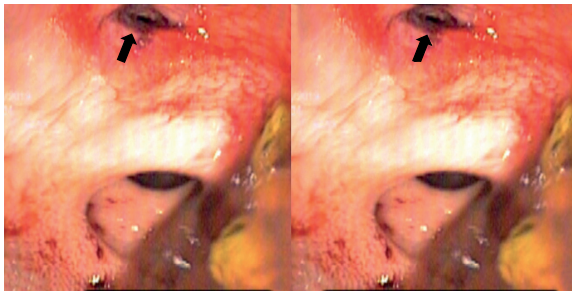

Por otro lado, la rectosigmoidoscopia permite la evaluación directa de la mucosa rectal, buscando hematomas, contusión, laceraciones o sangrado (Figuras 2 y 3), sin embargo, una mala preparación intestinal (escenario muy común en los pacientes con trauma) puede limitar su rendimiento diagnóstico 12,19. Un estudio de 106 pacientes demostró una sensibilidad aún más baja (34 %) de la TC para evidenc iar lesiones de recto; en contraposición, encontró una sensibilidad del 94 % para la rectosigmoidoscopia sola y una sensibilidad del 97 % cuando se combinan las dos estrategias diagnósticas 19.